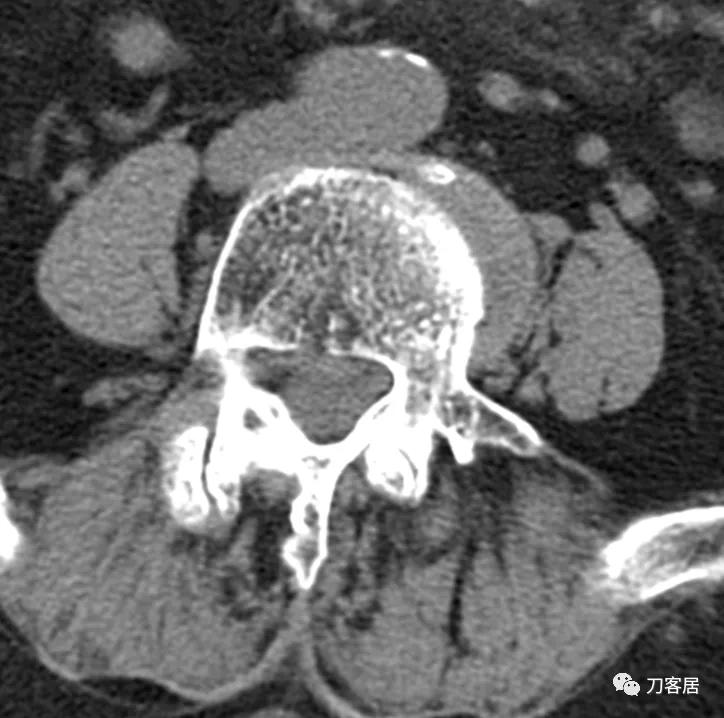

@胡满 如果是我的话,对于这种病例,首先抗骨质疏松治疗半年后再看情况,而且如果患者经济条件可以的话,建议直接使用特立帕肽,因为从患者的X线片来看,骨质疏松严重。患者的腰5滑脱应该是真性滑脱,腰5有峡部裂,腰4滑脱是退变滑脱,腰4-骶1椎管狭窄。但患者的痛苦不一定是椎管狭窄引起的。即使是做手术,患者的骨密度太低,钉子把持力不够。所以,先正规抗骨质疏松半年后再说手术吧。

@张西峰原*013院医** 是的,这个滑脱和椎管狭窄应该是几年甚或十几年,也可能是几十年以上的表现,但症状并没有那么久,手术现在做和过几个月做都是一样的,所以应该给患者以保守治疗的时间,而且这个患者骨质疏松是很明确的,应该正规抗骨质疏松一段时间后再看情况决定下一步如何处理。

患者为69岁,女性, 就诊日期:2021年11月8日。因晨起腰痛2天,就诊当日有缓解。疼痛自腰部放射至大腿后侧。2004-2005年曾有腰椎骨折病史,保守治疗后愈。

腰椎X线片提示腰5峡部裂,腰5椎体前滑脱1度,膝关节X线片提示退变增生,右侧髌股关节增生、狭窄、骨刺形成。骨密度提示骨质疏松,T值最低-3.3。2014年曾换心脏瓣膜手术,长期服用华法林,辅酶Q10, 盐酸曲美他嗪。

诊断:骨质疏松症,腰5峡部裂,腰5椎体前滑脱1度,双膝关节创伤性关节炎。